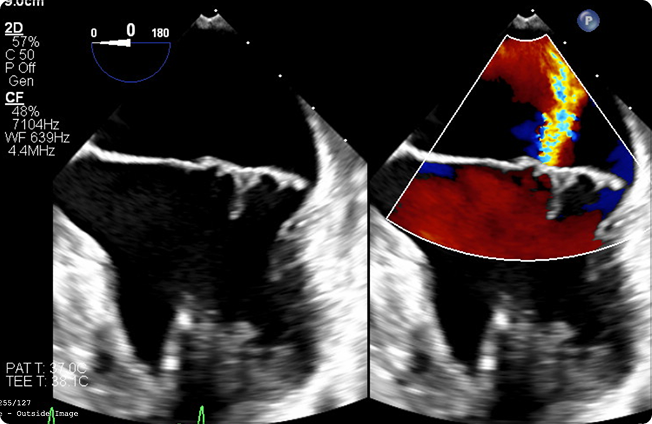

Ultrasound image showing a grayscale and color Doppler view of a heart, highlighting blood flow within the cardiac chambers.

Direct Image Integration

• View raw DICOM and other imaging files directly in VerixAi—no external software needed. Imaging data syncs with clinical records for seamless, context-rich expert review.